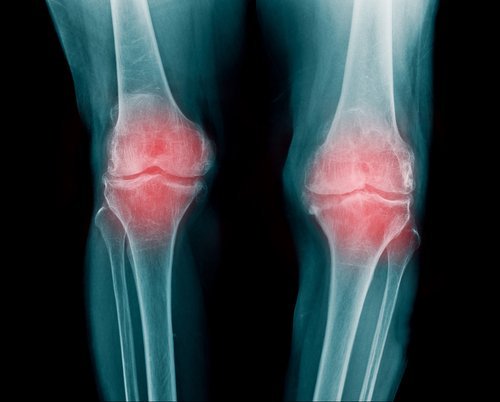

Artrite reumatoide

È un’infiammazione delle articolazioni e può manifestarsi in modi diversi. Generalmente le articolazioni più colpite sono le dita, le braccia e le ginocchia

Compare solitamente tra i 30 e i 60 anni ed è più frequente tra le donne che tra gli uomini. Non esistono differenze etniche o geografiche. Le persone che ne soffrono sperimentano una riduzione della loro capacità di movimento. Dopo un periodo di formicolio è possibile che appaiano dolori più forti.